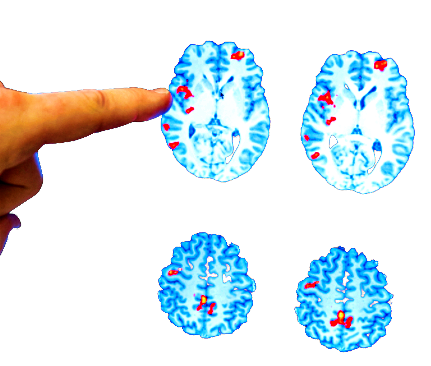

L’intensa immunosoppressione seguita da trapianto autologo di cellule staminali ematopoietiche blocca la progressione della malattia della sclerosi multipla. Lo ha rivelato uno studio malattia pubblicato sulla rivista Neurology e coordinato dall’ Ospedale Policlinico San Martino e dal Dipartimento di Neuroscienze, Riabilitazione, Oftalmologia, Genetica e Scienze Materno-Infantili dell’Università di Genova.

Lo studio del Prof. Gianluigi Mancardi e del Dott. Giacomo Boffa, ha coinvolto 20 centri italiani. Sono stati studiati tutti i pazienti con sclerosi multipla aggressiva che hanno subito un trapianto in Italia dal 1998 al 2019 che sono stati seguiti per un follow up medio di circa 6 anni. “I dati dimostrano che oltre il 60% dei pazienti non ha un aggravamento della disabilità dopo 10 anni dal trapianto e in molti casi si osserva anche un miglioramento del quadro neurologico duraturo nel tempo”, spiega l’Ospedale San Martino in una nota. “I risultati ottenuti sono di fondamentale importanza nel contesto attuale della malattia”, spiega Boffa.